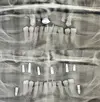

Implant tedavisi